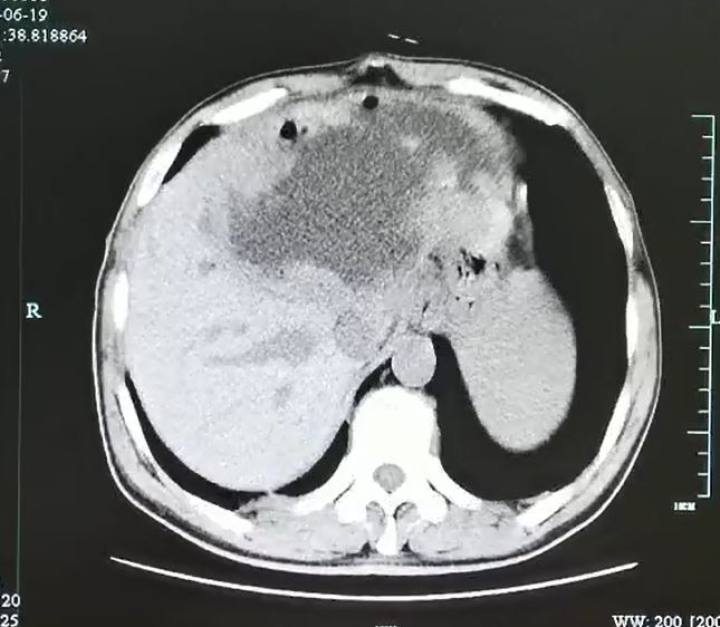

这一检查可把医生和谢师傅都吓坏了,

因为超声影像科检查显示

谢师傅的左肝已经被“掏空”了,

变成了一个大脓球

医生仔细测量了一下,

大脓球达到19cm×18cm×12cm 大小。

入院后腹部CT检查发现肝脓肿壁上长了很多肿瘤样的结构,而且壁很厚看来这个肝脓肿不简单。

经过三周的引流和保守治疗,复查增强CT发现谢师傅左肝的脓肿小了一大半,但是肝脓肿厚壁及厚壁上的很多肿瘤样组织没有变化,引流管里引流出来的液体开始减少,而且脓腔也不再进一步缩小,显示出这个脓肿很难自愈。